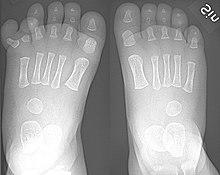

Toes.jpg

Toes on the human foot. The innermost toe (bottom-left in image), which is normally called the big toe, is the hallux.